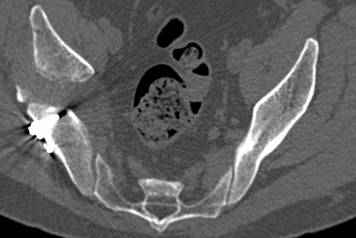

высылаю дополнительно сканы.

Судя по представленным реконструкциям (не очень хорошего качества - много наводок)

мы имеем дело с полупоперечным переломом у которого отломался задний край или его отломали, превратив перелом в полный двухколонный.

По отдельным срезам и тем более по реконструкции трудно судить о сращении крыла и задней колонны с осевым скелетом.

Все выступающие коллеги высказались насчет необходимости стандартных снимков по Judet, потому что для определения тактики лечения переломов вертлужной впадины 3Д снимки малоинформативны.

Из того минимума, что представлено, мне кажется, мы имеем дело с двухколонным переломом вертлужной впадины. Обычно медиальный (центральный) "вывих" головки встречаются в сложных двухколонных переломах со смещением.

Дополнительные сканы